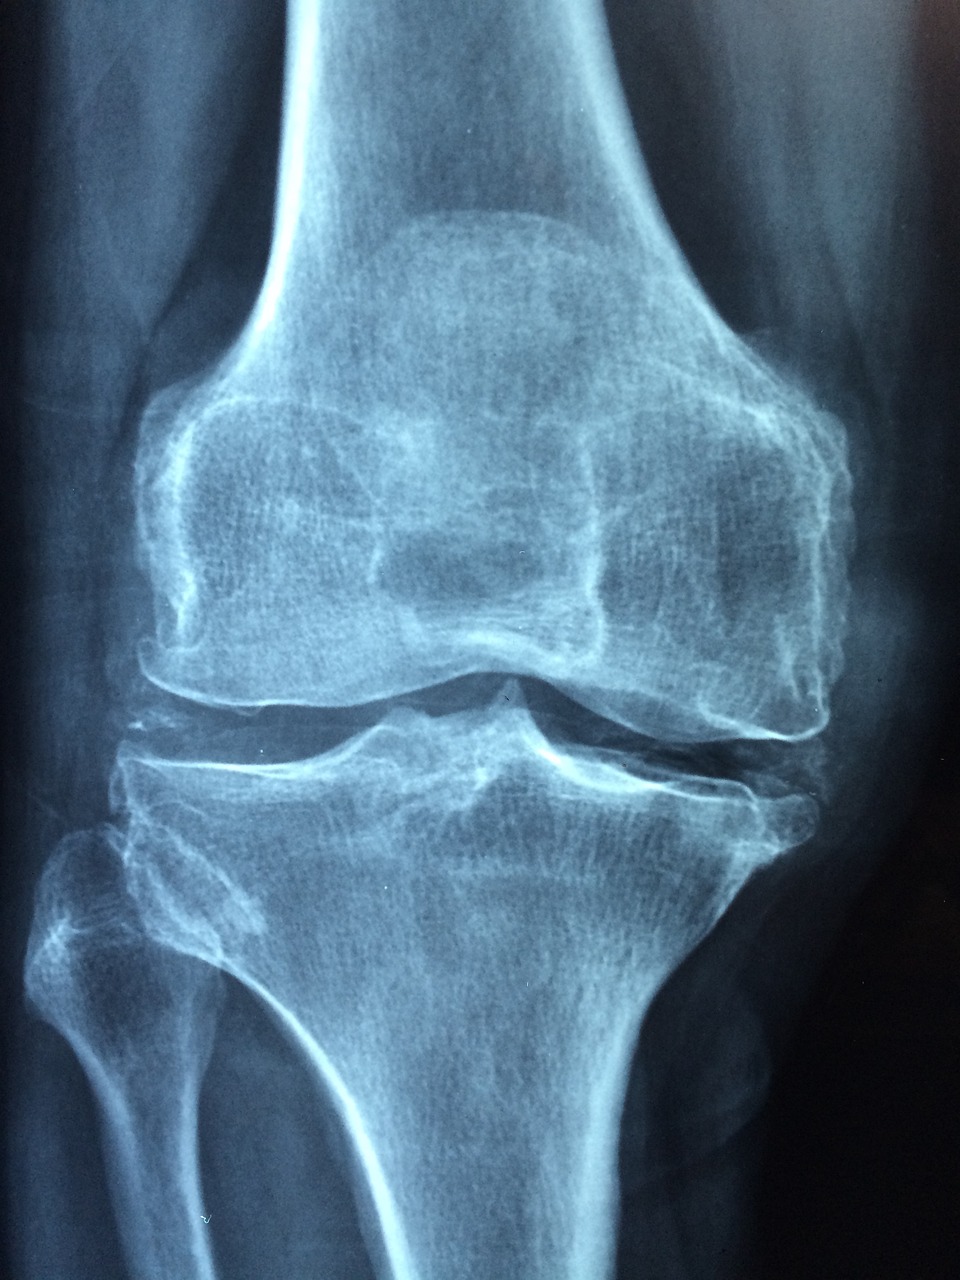

관절염은 천편일률적인 질환이 아닙니다. 여러 종류가 있는데 각각의 특징이 있습니다. 골관절염, 류마티스 관절염, 건선성 관절염이 대표적입니다. 골관절염은 흔히 노화와 관련이 있는데, 관절 연골이 파괴되는 것입니다. 그런데 류마티스 관절염은 우리 몸의 면역체계가 잘못해서 관절 조직을 공격하는 자가면역질환입니다. 건선 환자에게서 흔히 발생하는 건선성 관절염은 피부 병변을 동반한 관절통으로 나타납니다. 효과적인 관리를 위해서는 관절염의 종류를 이해하는 것이 중요합니다. 골관절염은 이런 유형으로 더 깊이 파고들면 서서히 진행되는데, 특히 활동을 하지 않는 기간이 지나면 통증과 경직을 유발합니다. 반면 류마티스 관절염은 여러 관절에 대칭적으로 영향을 미치는 경향이 있으며, 치료하지 않으면 관절의 기형을 유발할 수 있습니다. 건선성 관절염은 만성 피부 질환인 건선과 연관이 있다는 점이 특이합니다. 의료 전문가들은 특정 유형의 관절염을 찾아냄으로써 근본적인 원인을 해결하기 위한 치료 계획을 맞춤형으로 조정할 수 있으며, 이를 통해 환자들이 증상을 관리할 수 있는 보다 목표적이고 효과적인 방법을 제공합니다.

관절통은 관절염의 특징이지만, 관련된 다른 증상들을 인지하는 것이 중요합니다. 아침 경직, 붓기, 관절 가동 범위 감소 등이 대표적인 증상입니다. 또한, 관절염은 피로감과 함께 전반적인 불쾌감을 동반할 수 있습니다. 이러한 증상들은 종종 강도에 따라 변화하며, 개인의 일상 활동 능력에 영향을 미칩니다. 이러한 증상에 대한 인식을 강화하고, 사람들이 신속하게 의사의 진료를 받도록 유도하는 것이 조기 개입의 핵심입니다. 관절통은 공통된 증상이지만 구체적인 내용은 관절염의 종류에 따라 다릅니다. 골관절염은 주로 무릎과 엉덩이 같은 체중을 견디는 관절에 영향을 미쳐 국소적인 통증을 유발합니다. 류마티스 관절염은 전신적인 증상으로 여러 관절에 동시에 염증이 발생할 수 있습니다. 건선성 관절염은 축방향 골격과 주변 관절을 모두 포함할 수 있습니다. 개인은 증상의 미묘한 표현을 이해함으로써 정확한 진단과 적시에 개입할 수 있는 귀중한 정보를 의료 기관에 제공할 수 있습니다.